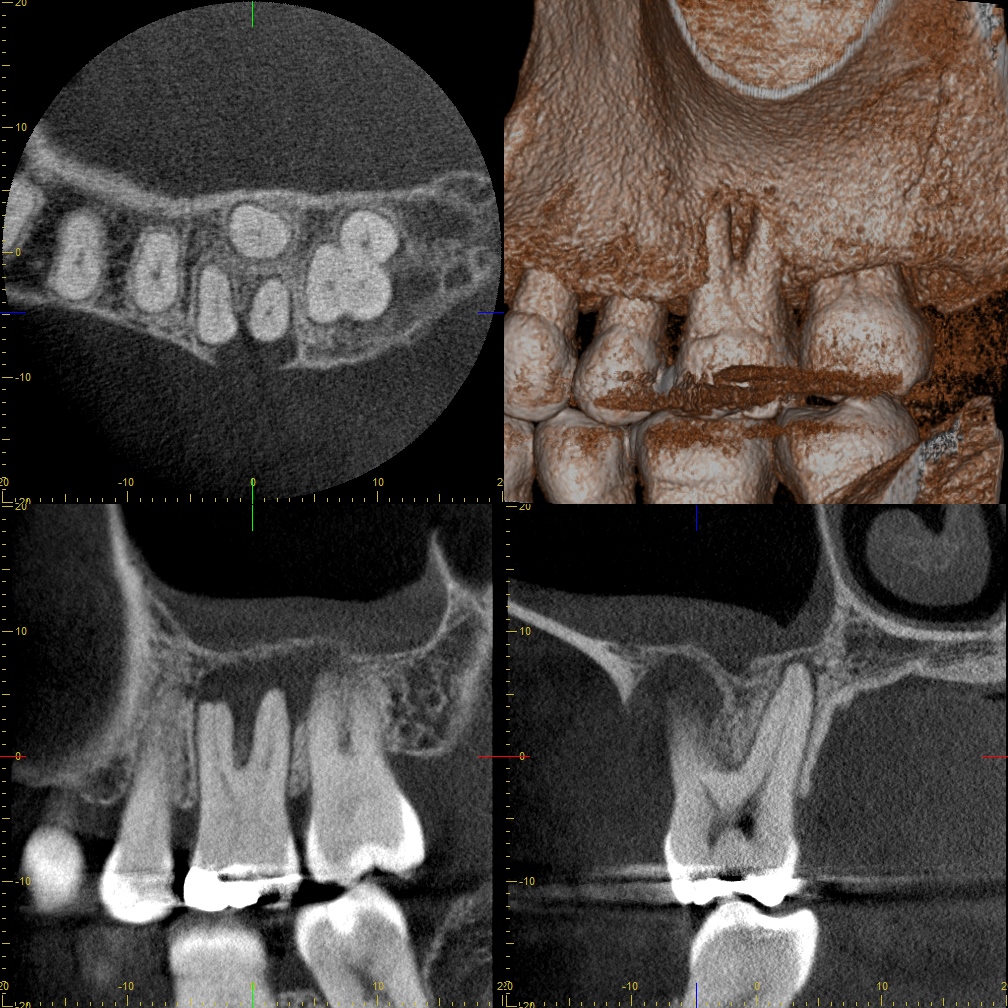

その後にX線検査やCT検査など必要に応じて画像検査を行います。